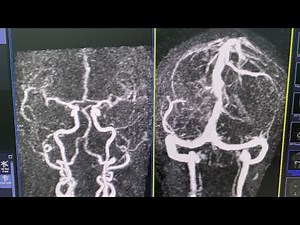

TWIST MRI or TRICKS

Radiologyscience Network: TWIST (Time-resolved angiography With Interleaved Stochastic Trajectories) is a time-resolved 3D MRA technique with very high temporal (sub-second) and spatial resolution (sub-millimeter) which will allow to capture the multiple arterial, mixed, venous phase images during the passage of a contrast agent through the ...

MRI TWIST BRAIN(Time-resolved angiography With Interleaved Stochastic Trajectories)MRA& MRV Contrast

MRI TWIST BRAIN(Time-resolved angiography With Interleaved Stoc